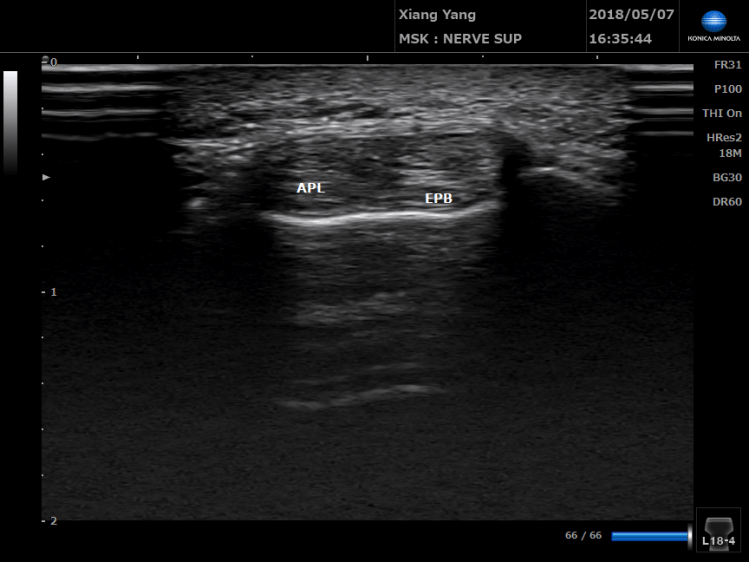

常被誤診為媽媽手的隔間症候群(Intersection syndrome)。

26歲男性,昨天玩傳說對決(DC超人),因為該角色操作需要反覆的手腕伸直和大拇指的動作,隔天手腕無法做往背側伸展的動作.

格肩症候群痛的位置比媽媽手還要在中間一點,除了打針與物理治療以外,使用貼紮減少肌腱的用力。可以更快回到正常工作。